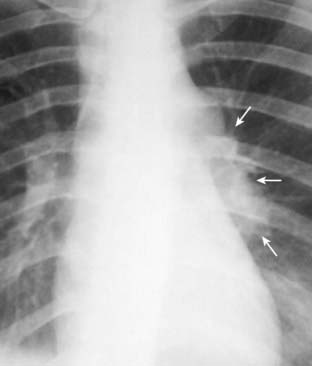

Figure 7-7 Primary tuberculosis.

There is prominence of the left hilum that is caused by left hilar adenopathy (solid white arrows). Unilateral hilar adenopathy may be the only manifestation of primary infection with Mycobacterium tuberculosis, especially in children. When it produces pneumonia, primary TB affects the upper lobes slightly more than the lower. It produces airspace disease that may be associated with ipsilateral hilar adenopathy (especially in children) and large, often unilateral, pleural effusions (especially in adults).